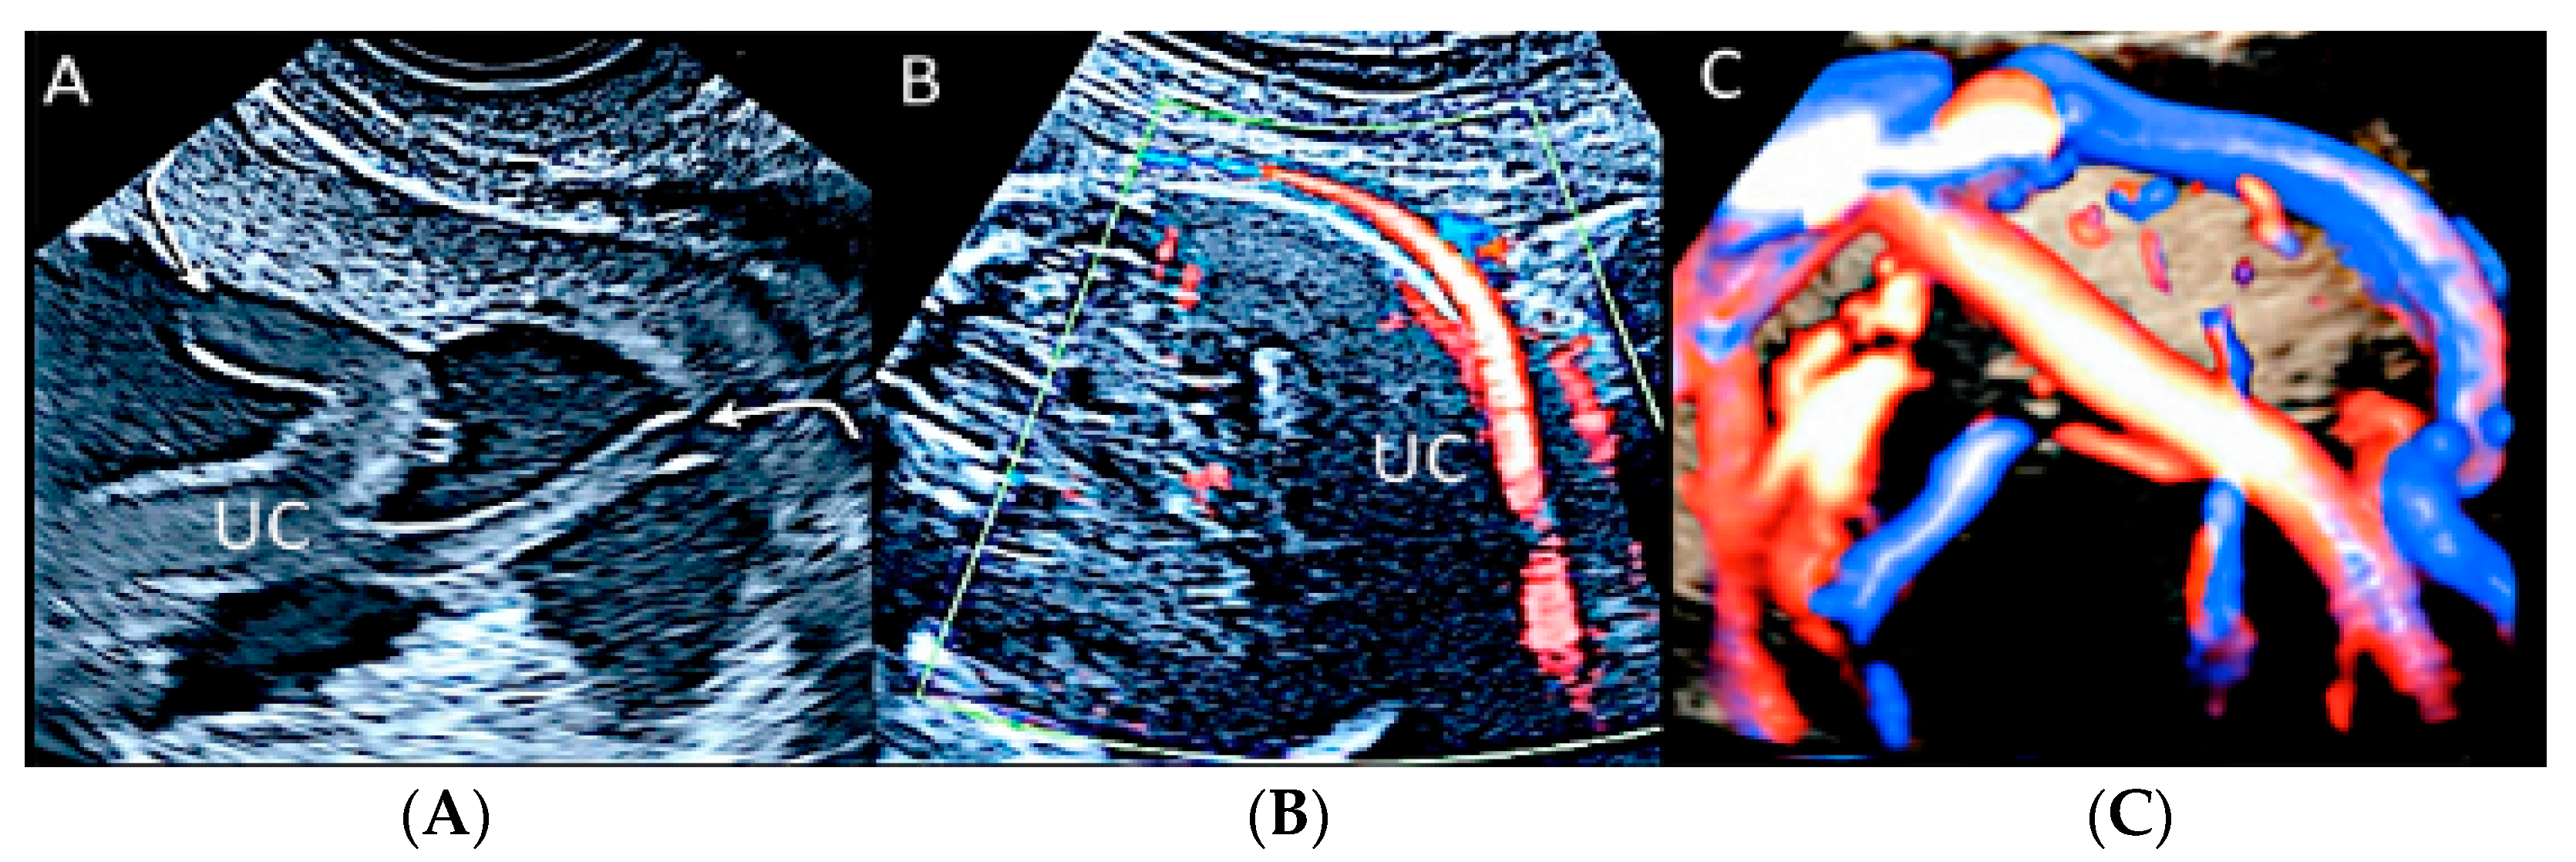

3.2.1. Nuchal Cords

3.2.6. Umbilical Cord Entanglement

3.2.7. Umbilical Cord Hemangioma